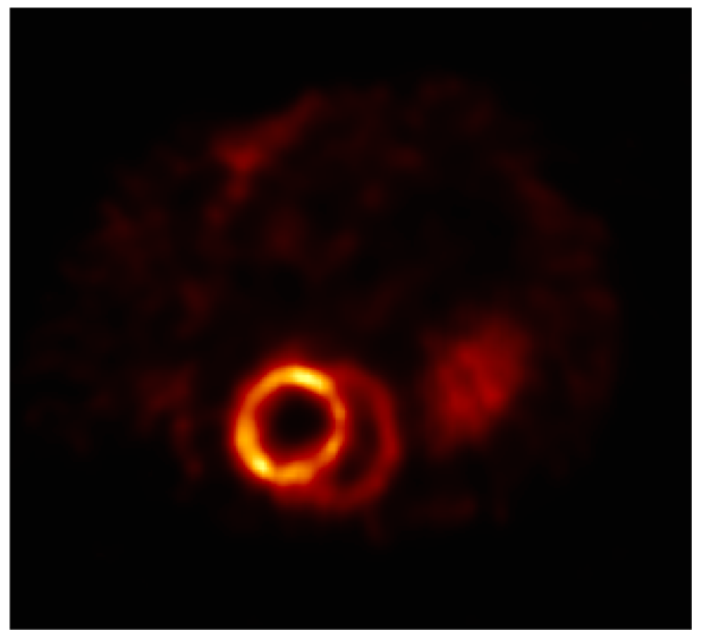

4、腎臟SPECT成像

不同放射性劑量的SPECT圖像對(duì)比:小鼠腎臟成像,[99mTc]DMSA,只對(duì)腎皮質(zhì)成像,說明可以低劑量成像。

腎臟成像.png